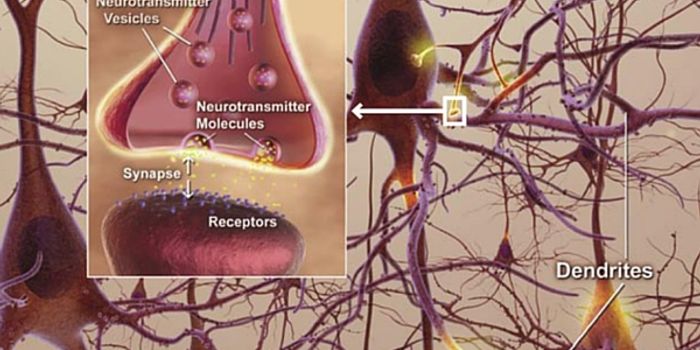

JUN 21, 2016NeuroscienceThe brain has always been referred to as the super computer of the body. Millions of connections happen just to make a s ...

MAR 01, 2016NeuroscienceThe vast network of neurons, dendrites, axons and other hardware that is responsible for sending messages all over the b ...

FEB 01, 2016NeuroscienceNeurons are incredibly tiny, but they have a big task in the brain. Cells within the nervous system, called neurons, are ...

JAN 20, 2016NeuroscienceThe brain is pretty much the body’s supercomputer. While the heart keeps blood pumping, the lungs keep air flowing ...